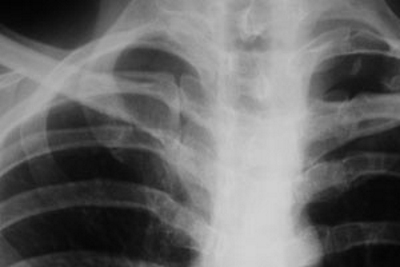

Перед началом терапии пациенту назначается ряд диагностических процедур:

- прослушивание и перкуссия грудной клетки, визуальный осмотр;

- рентгенография;

- ультразвуковое исследование грудной клетки для выявления внутренних повреждений;

- магнитно-резонансная томография — позволяет оценить травмы костных и мягких тканей, а также сосудов.